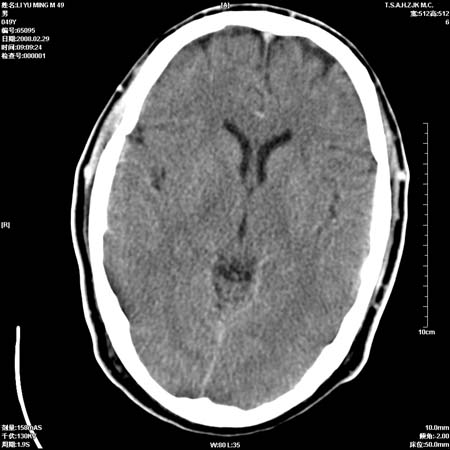

一周后复查ct:

可能为正常。间隔一周蛛血应基本吸收;再过一周复还是这样应该可以肯定了。

一周时间密度未见改变,考虑为正常图像(脑动脉硬化?)。